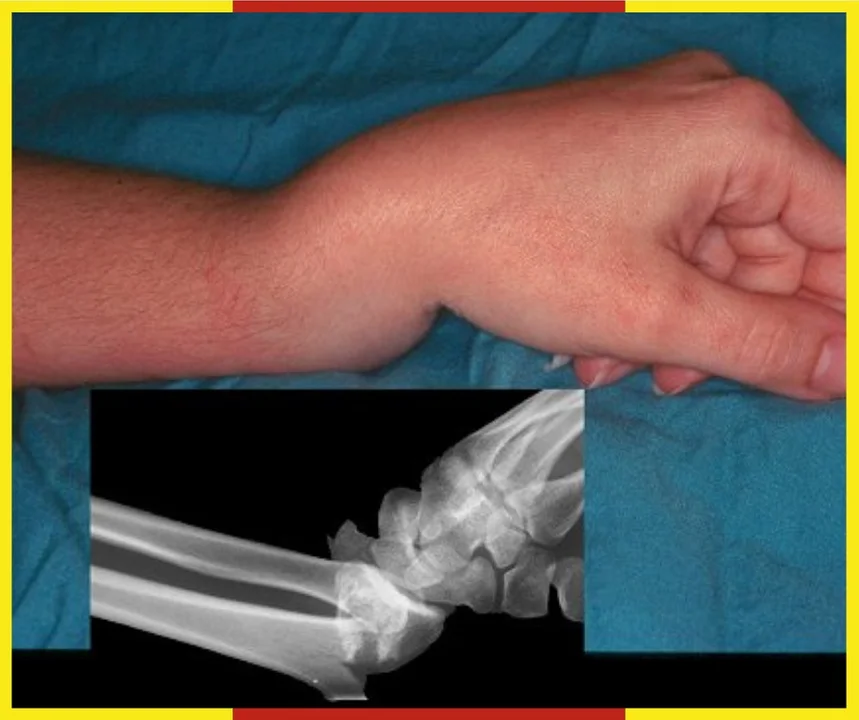

- W sezonie zimowym jednym z najczęstszych urazów związanych z upadkiem na oblodzonym chodniku jest złamanie Collesa — charakterystyczne złamanie dalszej nasady kości promieniowej. Dochodzi do niego zwykle wtedy, gdy podczas poślizgnięcia odruchowo wyciągamy rękę, by zamortyzować upadek.

Jak tłumaczą ratwonicy, jest to uraz bolesny i często wymagający dłuższej rehabilitacji. Szczególnie narażone są osoby starsze, u których nawet pozornie niewielki upadek może prowadzić do poważnych konsekwencji.

- Prosimy o ostrożność: stawiajcie kroki wolniej, wybierajcie stabilne obuwie, a seniorom zapewniajcie dodatkowe wsparcie podczas wyjść z domu. Każdy uważny krok to mniej ryzyka i więcej bezpieczeństwa — apelują pracownicy WSRM w Łodzi.